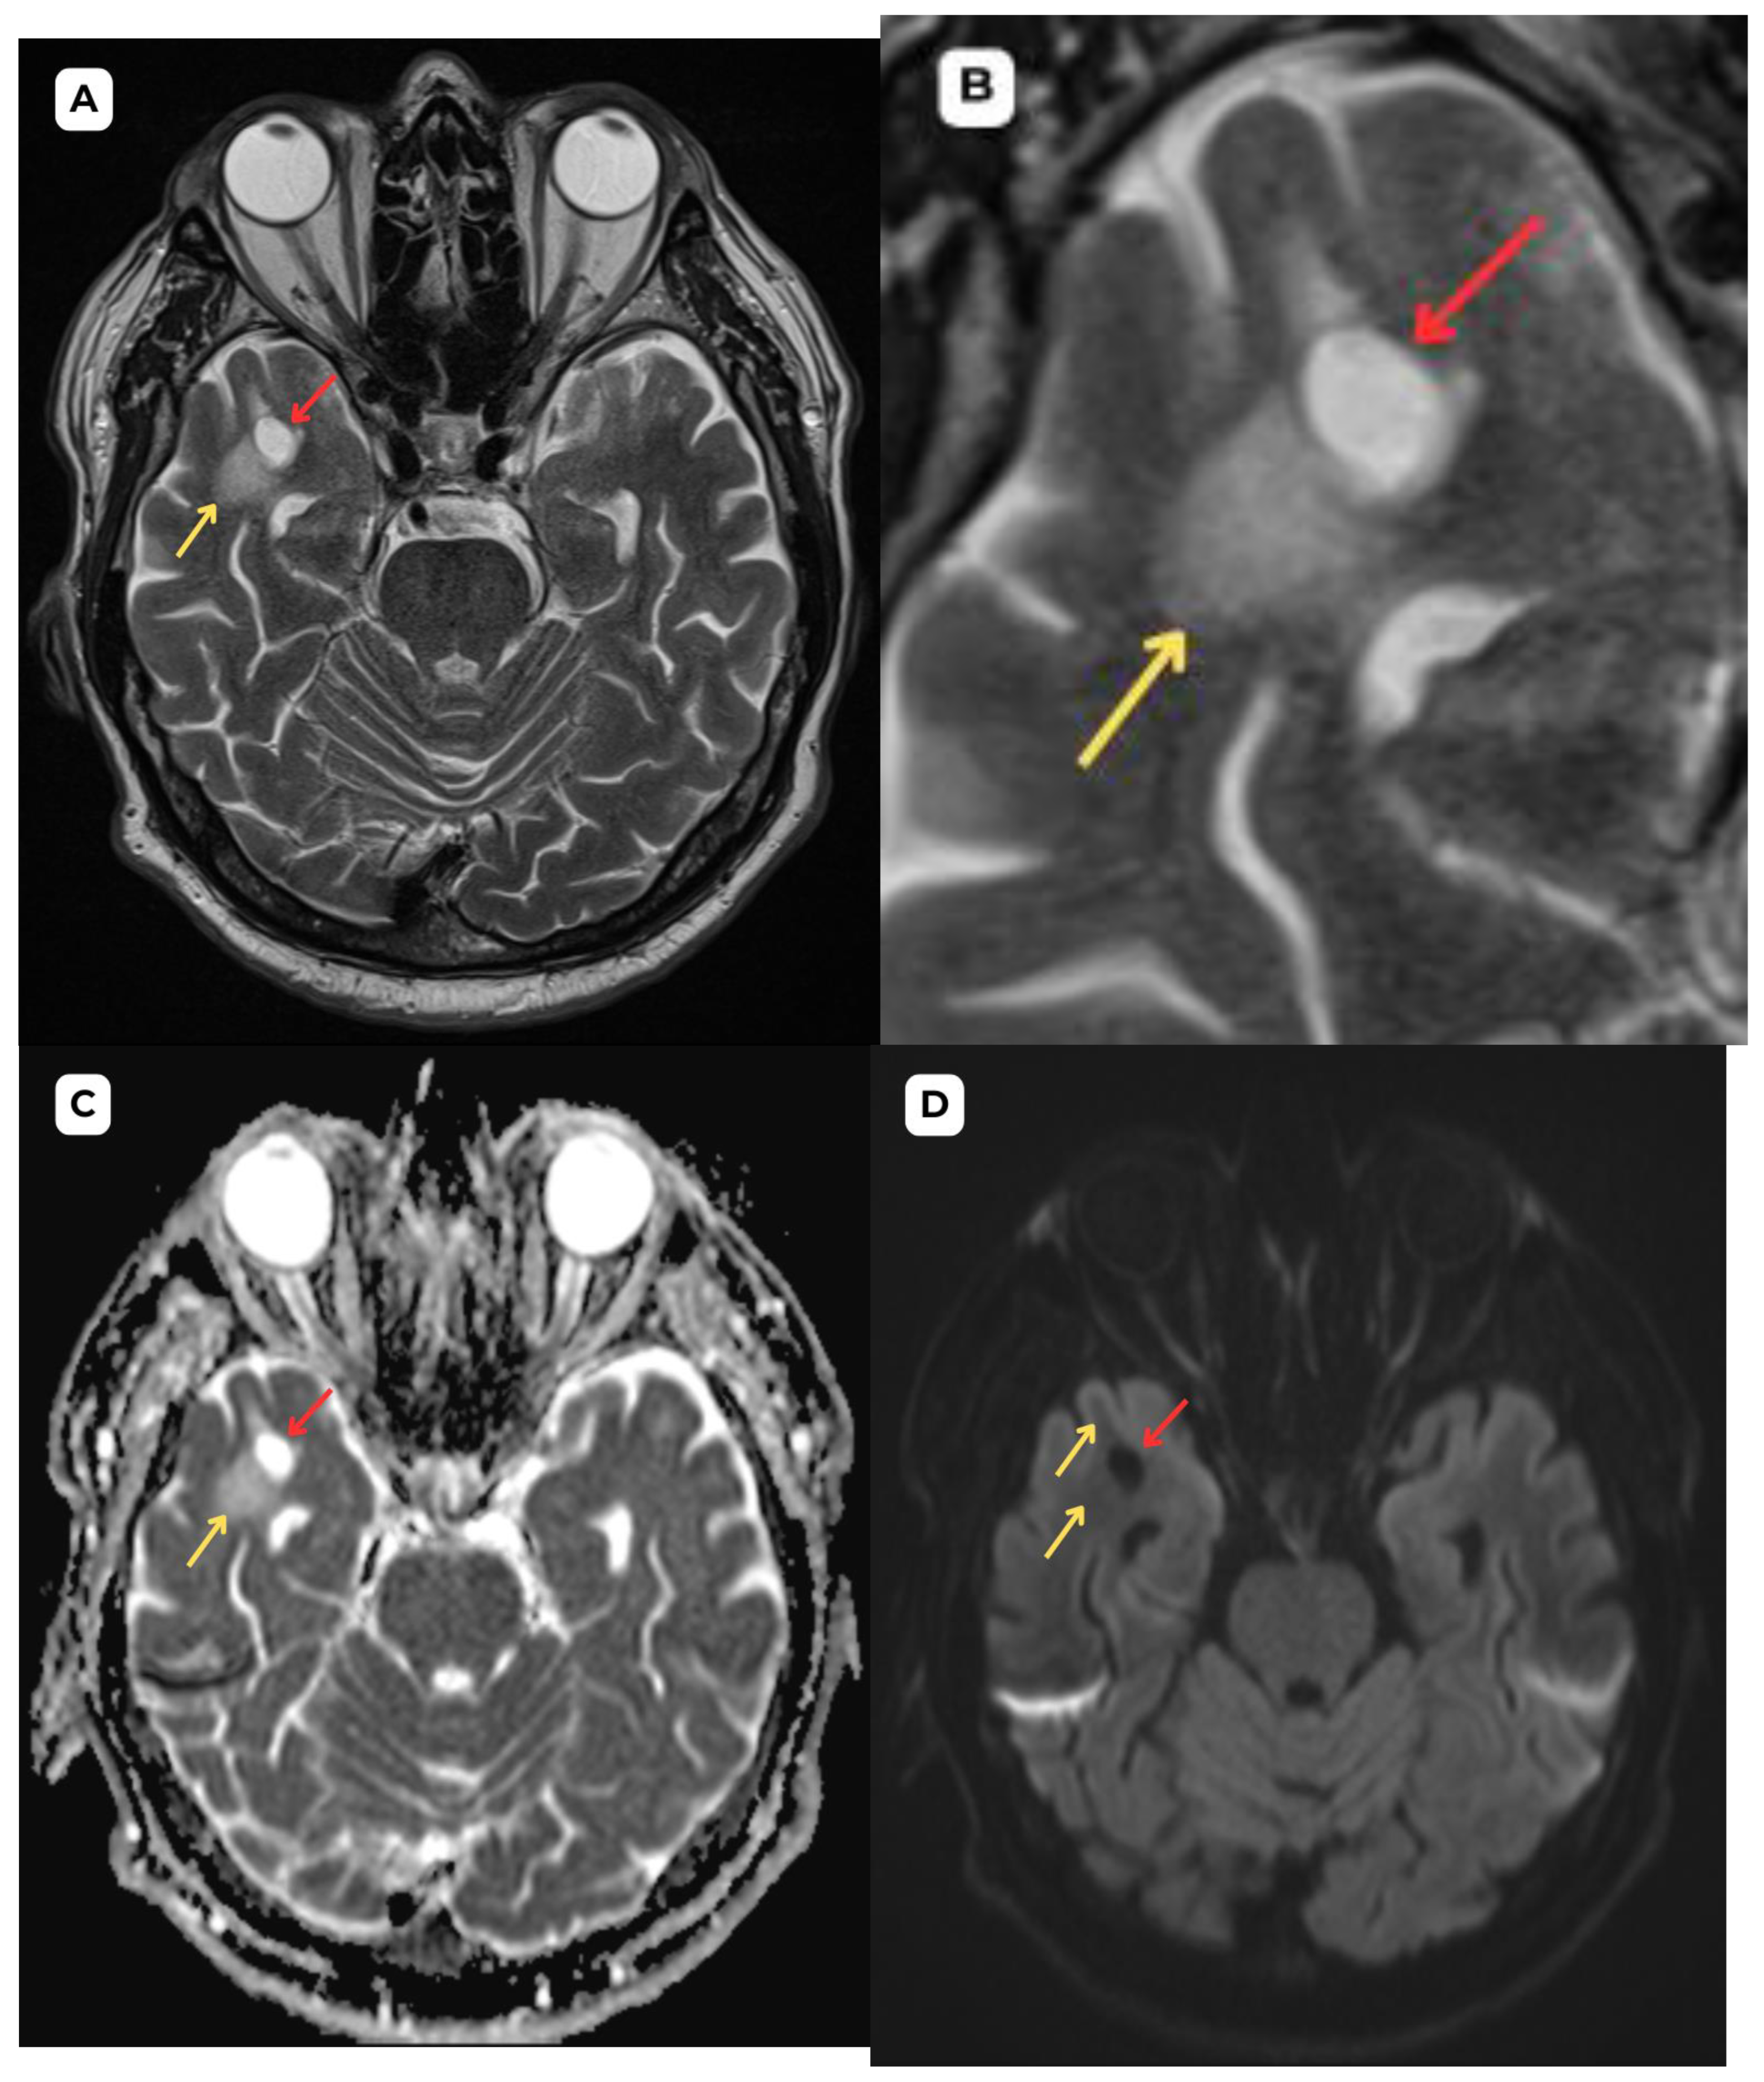

Figure 1. First patient: brain MRI of a 63-year-old male. (A): Axial T2-weighted sequence. A cystic lesion (red arrow) is seen in the anterior part of the superior temporal gyrus of the right temporal lobe, measuring 1.1 × 0.8 cm, accompanied by perifocal edema (yellow arrows) in the surrounding white matter. (B): Axial T2-FLAIR after contrast image at the corresponding level demonstrates improved visualization of the cerebrospinal fluid (CSF) content of the lesion (red arrow) and highlights the perifocal edema (yellow arrow) more clearly, without contrast enhancement. (C): ADC map shows high value with no diffusion restriction on (D): DWI-B1000, where changes show no signs of potential malignancy, most likely benign structural changes. The most likely differential diagnosis is opercular (type IV) perivascular space. Red arrow—opercular (type IV) perivascular space, yellow arrow—surrounding edema.

In magnetic resonance imaging, the signal intensity of the opercular perivascular spaces themselves is identical to that of cerebrospinal fluid in all sequences—hypointense on T1W1 and FLAIR, hyperintense on T2W1, and the ADC value corresponds to cerebrospinal fluid [6,7]. In both of these cases, MRI images were acquired with the Siemens “MAGNETOM Sola” 1.5T system. In both cases, cerebrospinal fluid signal is visible in all MRI sequences. In the images, these PVS are located very close to the branches of the middle cerebral artery, which come into contact with the cerebral cortex, with MRI showing regional cortical thinning in the brain [6,7].

The presence of cerebrospinal fluid intensity tracts in the images is also useful as a radiological criterion for the diagnosis of perivascular spaces [1]. All the above-mentioned features help distinguish opercular perivascular spaces from neuroglial tumors with characteristic perifocal edema.

In MRI imaging, opercular perivascular spaces can also be differentiated based on their appearance: round, oval, or tubular, well-defined cystic structures that do not contain calcifications, hemorrhagic elements, or high-protein content structures. In both cases, opercular perivascular spaces appear round (Figure 1, Figure 2, Figure 3, Figure 4, Figure 5 and Figure 6). These formations do not enhance with contrast, which also helps to distinguish them from other pathologies. In both of the cases no contrast enhancement was seen (Figure 1, Figure 2, Figure 3, Figure 4, Figure 5 and Figure 6). It is important to highlight the pathognomonic feature—visualization of the perforating central artery of the perivascular space—using TOF combined with 3D CISS sequences [8].